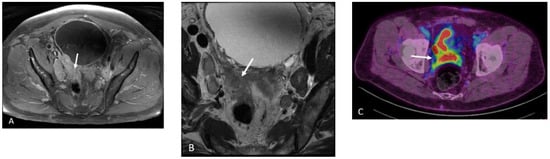

Detection of Loco-Regional Disease and Distant Metastases